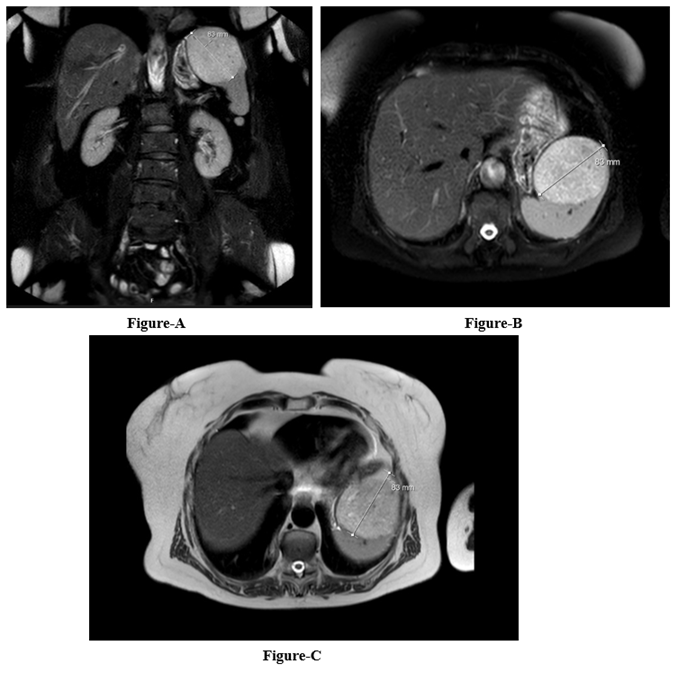

An ultrasound of the abdomen revealed moderate splenomegaly, measuring 140 mm craniocaudally, with a large, predominantly hyperechoic mass at the upper pole. The mass measured approximately 85 mm by 80 mm by 75 mm. Magnetic resonance imaging (MRI) of the abdomen was performed using a 1.5 T MRI (Ingenia; Philips Healthcare, Best, the Netherlands) in the coronal, axial, and sagittal planes, following the standard protocol. T2-weighted sequences in multiplanar reconstruction were used for evaluation. Respiratory-triggered T2 SPAIR axial and T2 coronal sequences with a slice thickness of 5 mm that comprise the entire abdomen were acquired. The MRI showed that the spleen was enlarged to 135 mm in length, with a large exophytic mass growing along the anterosuperior border. The mass measured 83 mm by 78 mm by 80 mm and appeared as a clearly demarcated, encapsulated, round, focal lesion that partially bulges the contour. On the native sequence set, the T1 (mDIXON) isosignal is moderately hypersignal with moderate diffusion restrictions, showing early visible post-contrast dynamics that are predominantly homogeneous already in the arterial phase, with uniform signal amplification in the venous phase and several smaller hyposignal zones within the lesion (Figure 1). According to the radiologist, this finding is highly likely to be benign, primarily of hamartomatous nature

Figure 1: The T2w-SPAIR sequence in the coronal (A) and axial (B) planes, as well as the T2w-TSE sequence in the axial (C) plane, show a splenic vascular tumor.